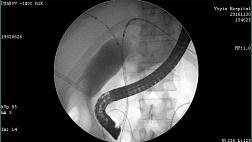

Иллюстрация №4: РХПГ при хроническом панкреатите (Изменения по типу "жемчужной нити")

Амилаза и липаза сыворотки может соответствовать норме или быть незначительно повышена. У 5-10 % пациентов с хроническим панкреатитом компрессия дистальной части общего желчного протока ведет к увеличению билирубина сыворотки и щелочной фосфотазы. Мальабсорбция жира ведет к увеличению его экскреции с калом (более 7 грамм в день). Выявление панкреатических кальцификатов при рентгенографии, УЗИ или компьютерной томографии является диагностическим критерием хронического панкреатита. Эти кальцификаты обнаруживаются в примерно 25-60 % всех случаев хронического алкогольного панкреатита и у 35-80 % пациентов с панкреатитом другой этиологии. Компьютерная томография может также выявить локальное увеличение размеров поджелудочной железы, ее атрофию, расширение панкреатического протока или псевдокисту. РХПГ является наиболее чувствительным и специфическим визуализирующим исследованием в диагностике хронического панкреатита (рис. 3).

Из-за риска развития панкреатита в результате выполнения РХПГ эта диагностическая процедура должна применяться только когда неинвазивные исследования являются малоинформативными. Новые, более современные виды исследований, как ядерно-резонансная холангиопанкреатография и эндоскопическое ультразвуковое исследование становятся все более популярными. Если с использованием всех этих визуализирующих исследований не удается подтвердить диагноз, то может быть выполнено тестирование функции поджелудочной железы со стимуляцией секретином или ХК [10]. Диагностический алгоритм приведен на рисунке 4.